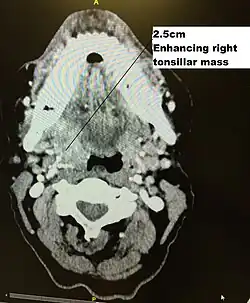

| Diagnostic method | Endoscopy, Biopsy, Staining for p16, CT Scan, |

Initial diagnosis requires visualisation of the tumour either through the mouth or endoscopically through the nose using a rhinoscope, illustrated to the right, followed by biopsy.

Staging

Staging is generally by the UICC/AJCC TNM (Tumour, Nodes, Metastases) system.[68] Staging is based on clinical examination, diagnostic imaging, and pathology. On imaging, involved lymph nodes may appear cystic, a characteristic of HPV+OPC.[69]